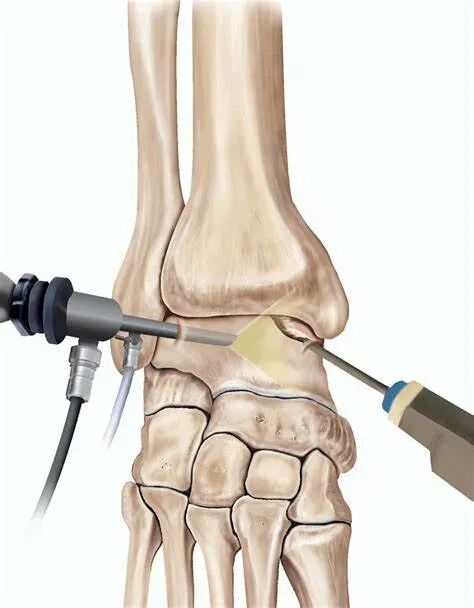

软骨成形术使用踝关节前侧关节镜标准入路,插入 2.3 或 2.7mm 镜头和探钩,检查软骨表面不规则处,区分软化 / 不稳定软骨(可能伴撕裂)与健康软骨。用刨刀(2.2、3.5 或 4.2mm)打磨纤维化软骨,注意保护周围健康组织。通过刨刀打磨软骨表面,平整粗糙面,避免软骨碎片脱落形成游离体影响关节活动,同时切除表面裂纹以减少损伤加深,通过消除不平整改善关节内负荷分布。

微骨折术通常与病变软骨清创联合进行,用刨刀去除缺损软骨层,必要时用锐匙修整至健康软骨边缘。去除软骨后暴露骨板,需判断骨板是否完整或存在额外骨缺损(骨软骨损伤),可用锐匙清理。钻孔器械包括专用工具或不同直径克氏针。纳米骨折术尖端直径 1mm,微骨折术尖端直径 2mm,器械尖端可弯曲 20-60° 以适应损伤部位,通过锤击形成微骨折,促使骨髓干细胞释放。研究表明,钻孔深度超过 9mm 可显著增加干细胞释放量。若损伤过大(2017 年标准已将临界值降至 1cm²),非负重腔隙不足以形成再生纤维软骨。